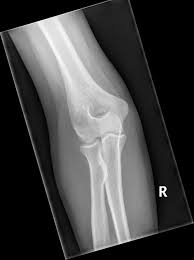

AP projction of elbow

lateral projction of elbow

45 degree medial oblique of elbow

45 degree lateral oblique of elbow